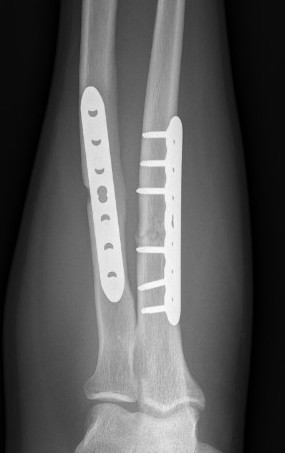

ORIF with DCP plates

Fixation with DCP plates